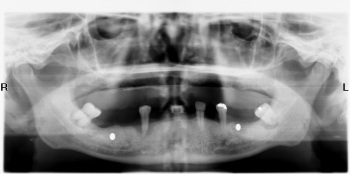

Hình bệnh lý u men. Xương hàm và chân răng bị tiêu biến ở góc trái hình.